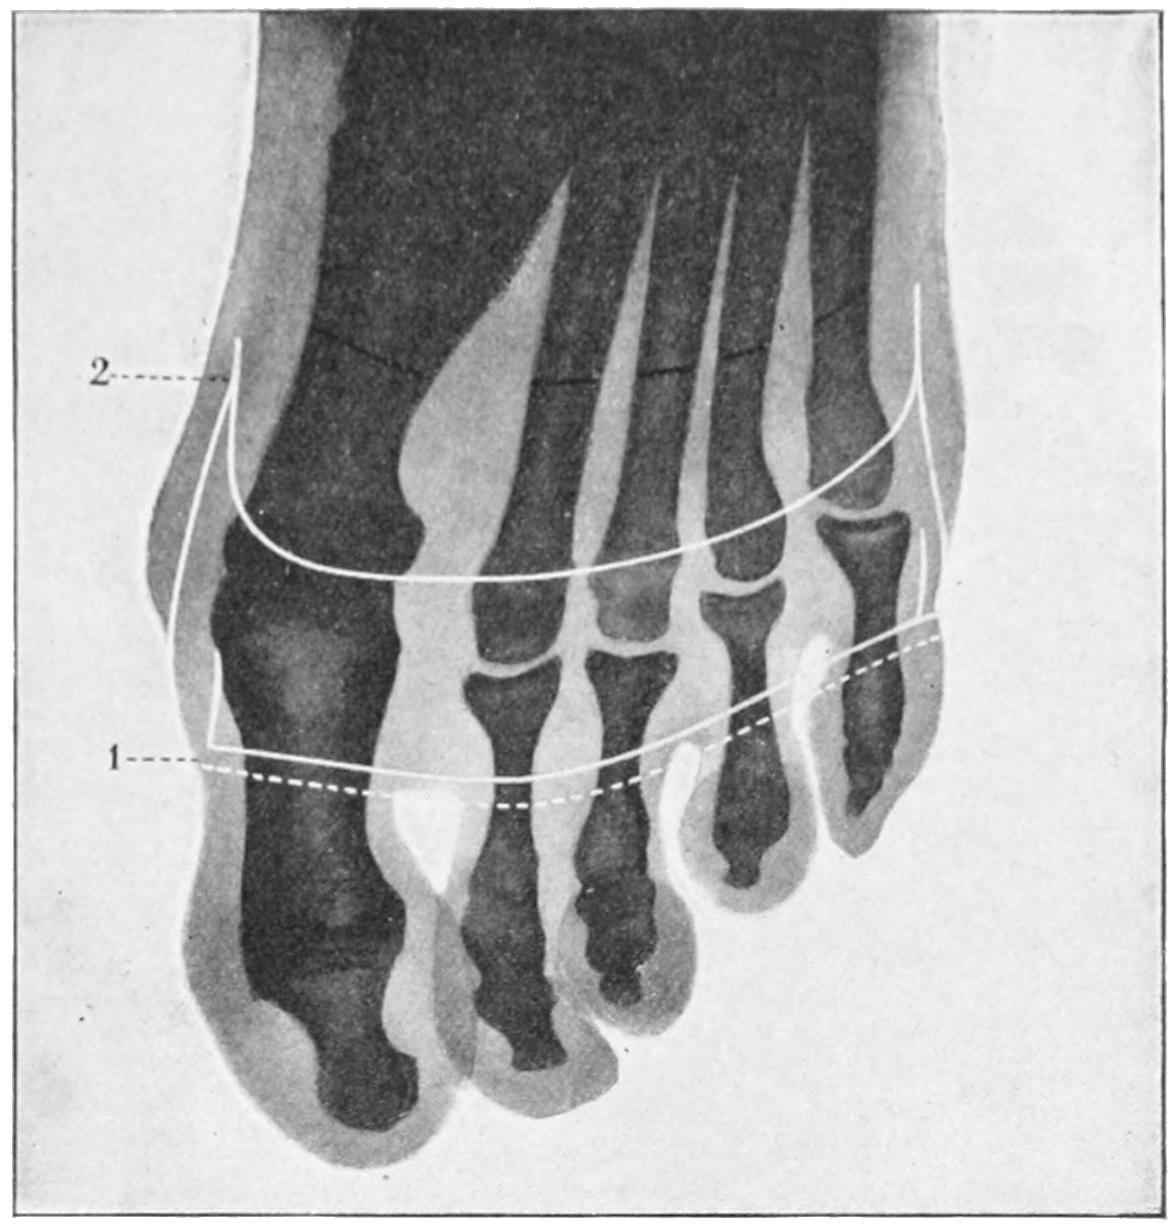

SURGICAL DISEASES OF THE OSSEOUS SYSTEM 416

DEFORMITIES DUE TO CONGENITAL DEFECTS OR ACQUIRED DISEASES OF THE LOCOMOTOR APPARATUS; ORTHOPEDICS 444

FRACTURES 479